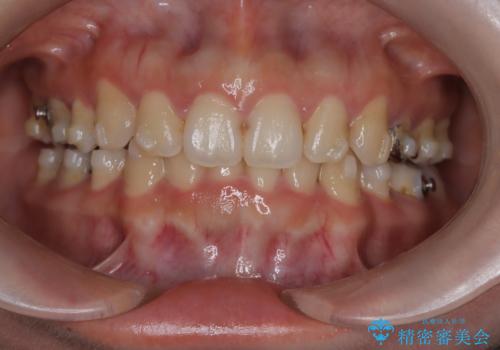

- 上下の歯の中心(正中)のズレと、口元の見た目を気にされて来院されました。精密な検査の結果、咬み合わせのバランスを整えながら、正中線を一致させる治療が必要と判断。患者様のご希望に合わせ、透明で目立ちにくいインビザライン(マウスピース矯正)による治療計画を立案しました。歯列全体を奥(遠心)へ移動させるためにゴムかけを併用。さらに、見た目を改善するため、既存の金属の被せ物をセラミッククラウンに交換することも治療計画に組み込みました。

今回の矯正治療では、透明なマウスピース型の装置インビザラインを使用しました。歯列を奥へ動かす遠心移動の効率を高めるため、患者様ご自身にゴムかけも行っていただきました。この併用によって、歯をより正確かつスムーズに動かすことができ、上下の歯の中心である正中線を一致させることが可能になりました。また、治療の最終段階では、以前から入っていた金属の被せ物を、天然歯に近い色合いのセラミッククラウンに交換。矯正治療と審美治療を組み合わせることで、機能的な咬み合わせの改善に加え、金属が見えない、より自然で美しい口元を獲得していただけました。